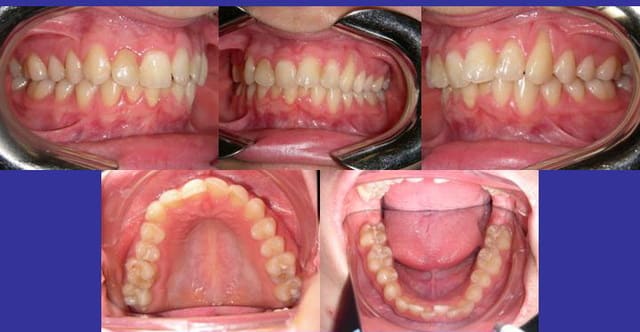

patient de 17 ans

tt odf vers 10 ans (plaque palatine puis MB H+B)

avulsions des 8 vers 15 ans.

souhaite des dents alignées.

Quelle attitude thérapeutique adopter ?

Ce qui serait tres interessant,ce serait d'avoir le dossier clinique initial a 10 ans avant de prendre une decision.

quelques éléments de réponse aux questions posée :

- il s'agit bien évidemment de rhizalyses dont la cause iatrogène orthodontique est plus que fortement suspectée : d'abord avec la plaque palatine dont je suppose qu'elle avait un rôle pour favoriser l'éruption de 23 (par désinclusion ? je l'ignore)dont le manque de place et l'éruption haute ont laissé une dénudation radiculaire importante ainsi que l'occlusion non fonctionnelle venant ajouter la sanction finale.

De plus il s'agit (s'agissait) d'une CL II.2 dont lors du TT Mb , la demande en torque incisif de par la pression labio-jugale est intense et accroit le risque de rhizalyse.

- Je n'ai aucun documents avant ceux-ci car vous l'aurez compris, l'objet de la consultation est un 2e avis ..après avoir eu celui du praticien qui a réalisé le TT. Avoir le dossier clinique initial serait intéressant pour savoir d'où l'on est parti, bien sûr, mais il y a une décision à prendre maintenant qui selon moi ne dépend pas de la situation initiale.

- la mobilité des incisives < et > est de stade 1 (0.2 à 1 mm horizontal)

Je vous livre la réflexion que j'ai eue sur ce cas et l'attitude thérapeutique:

- on objective au moins 6 incisives rhizalysées soit un peu moins de 1/4 de la denture

- contexte CL II,2, hypodivergent, hypertonicité musculaire labio-jugale.

- nécessité d'ingression et d'hypertorque incisif qui est un facteur aggravant dans les rhizalyses.

- nous voyons que la récidive est rapide et sévère après un 1er TT.

- la notion de bénéfice / risque doit impérativement être évaluée dans ce contexte.

C'est ce dernier point qui pour moi pése dans la conduite à tenir.

J'ai décidé de ne pas (re)traiter ce patient car j'ai estimé que malgré l'utilisation de la technique non ligaturante (force et frottement faible) le risque de nouvelles rhizalyses est important vu des antécédents et de la demande en torque sur les incives.

Un traitement n'est pas interdit mais le jeu en vaut il la chandelle? Ce n'est pas mon sentiment.